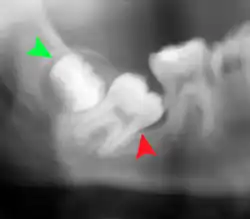

Coronectomy

Coronectomy is a procedure where the crown of the impacted wisdom tooth is removed, but the roots are intentionally left in place. It is indicated when there is no disease of the dental pulp or infection around the crown of the tooth, and there is a high risk of inferior alveolar nerve injury.[36]

Coronectomy, while lessening the immediate risk to the inferior alveolar nerve function has its own complication rates and can result in repeated surgeries. Between 2.3% and 38.3% of roots loosen during the procedure and need to be removed and up to 4.9% of cases require reoperation due to persistent pain, root exposure or persistent infection. The roots have also been reported to migrate in 13.2% to 85.9% of cases.[36]